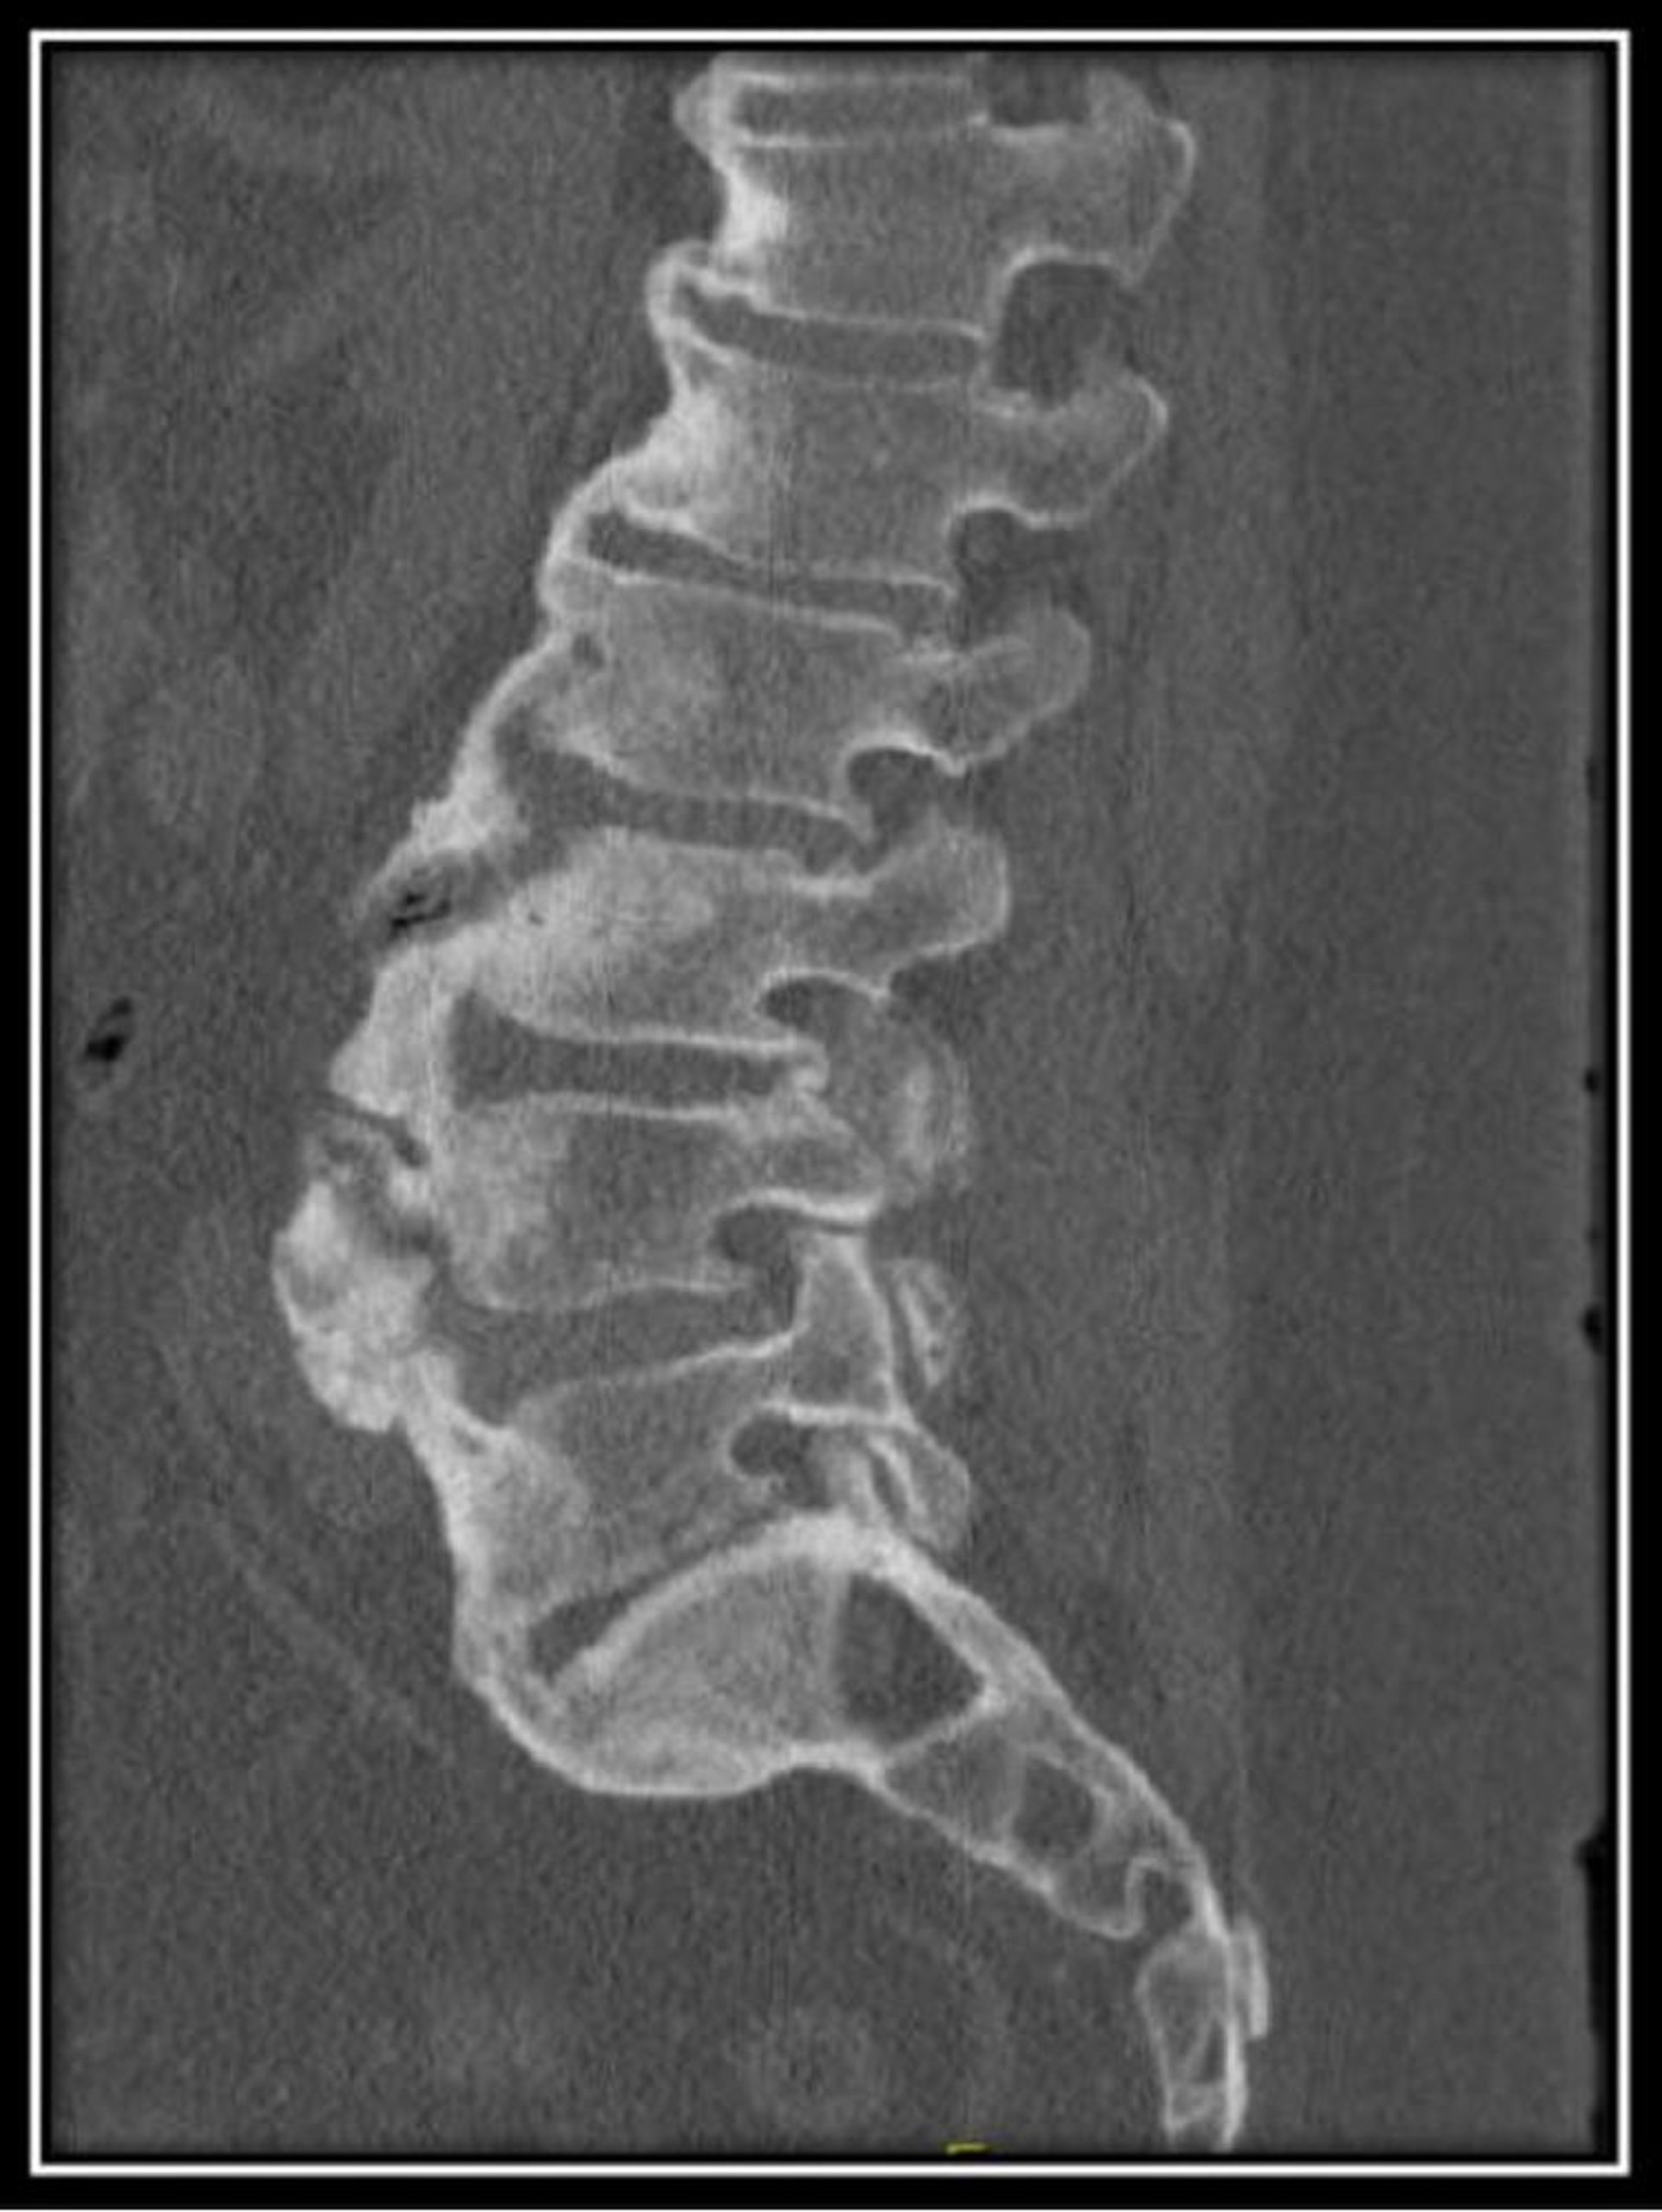

Hiperostose esquelética idiopática difusa (TC)

Essa TC da parte lombar da coluna em um paciente com hiperostose esquelética difusa idiopática mostra alturas normais dos corpos vertebrais com osteófitos de fluxo anterior difusos e espaços discais preservados.

Imagem cedida por cortesia de Kinanah Yaseen, MD.